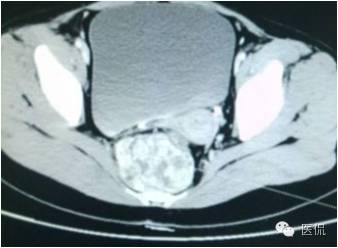

增强静脉期(CT值62HU)

增强延迟期(CT值106HU)

手术是:盆腔占位,病理为:血管肌纤维母细胞瘤。与肛门粘连,于是同时做了肛门的处理。